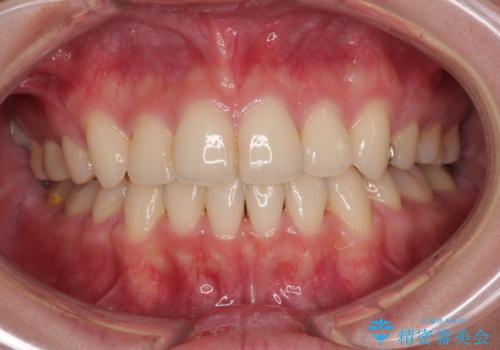

歯並びのせいで歯ブラシがしづらい マルチブラケットを用いた抜歯矯正

担当医 大元洋佑